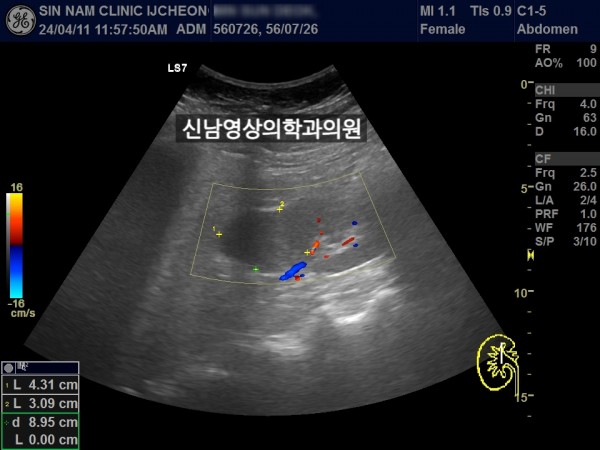

좌측 신장 지방혈관종 추적검사中 우측 신장의 종괴를 발견했습니다.

차후 신장암으로 수술하셨습니다.

초음파 당시 증세는 없었습니다.